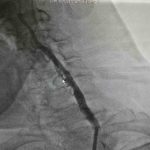

Samsun’da yaşayan Zekai Bozyel (71), 15 yıl önce bypass ve kalp kapak ameliyatı geçirdi. Rutin kontrolleri devam eden Bozyel, 20 gün önce kolunda güçsüzlük şikayetiyle nöroloji servisine yatırıldı. Yapılan tetkiklerde hastanın sağ boyun damarında yüzde 30, sol boyun damarında ise yüzde 90 oranında darlık tespit edildi. Sol taraftaki ciddi darlığın hastanın felç geçirmesine neden olduğu belirlendi. Hastanın daha önce kronik akciğer rahatsızlığı bulunması ve geçirdiği ameliyatlar nedeniyle anestezi açısından yüksek risk taşıdığı değerlendirildi. Bunun üzerine hastanın durumu kardiyoloji ekibi tarafından yeniden ele alındı. Akabinde Medicana International Samsun Hastanesi Kardiyoloji Uzmanı Dr. Öğr. Üyesi Ahmet Yanık, boyun damarında yüzde 90 darlık tespit edilen ve daha önce baypas ile kalp kapak ameliyatı geçiren hastaya ameliyatla kasıktan girerek uygulanan anjiyografik yöntemle stent yerleştirdi. Gerçekleştirilen başarılı müdahaleyle yeniden felç riskinin önüne geçildiğini belirtti.

Hastanın filmlerini inceleyip muayenesini yaptıklarını belirten Dr. Öğr. Üyesi Ahmet Yanık, “Zekai bey 15 yıl önce bypass ve kalp kapak ameliyatı olmuş, rutin takiplerinde devam eden bir hastamız. 20 gün önce nöroloji servisine yatıyor. İnme hikayesi ve kolunda güçsüzlük var. Yapılan tetkiklerinde boyun damarında darlık saptanıyor. Sağdaki boyun damarında yüzde 30, soldaki boyun damarında ise yüzde 90 civarında bir darlık var. Bu felç geçirmesine sebep olan bir darlık. Öncelikle ameliyat düşünüldü ancak kronik akciğer öyküsü ve diğer rahatsızlıkları nedeniyle anestezi açısından riskli bulundu. Biz damarın bu şekilde bırakılmasının daha riskli olacağını düşündük. Hastamızla görüşerek işlemi yapmaya karar verdik. Başarılı bir şekilde soldaki boyun damarına kasıktan girerek, herhangi bir kesi yapmadan anjiyografik olarak stent yerleştirdik. İşlem sonrası herhangi bir sorun yaşamadık ve hastamızı taburcu ettik. Müdahale edilmemesi durumunda daha ciddi bir felç riski söz konusuydu” dedi.